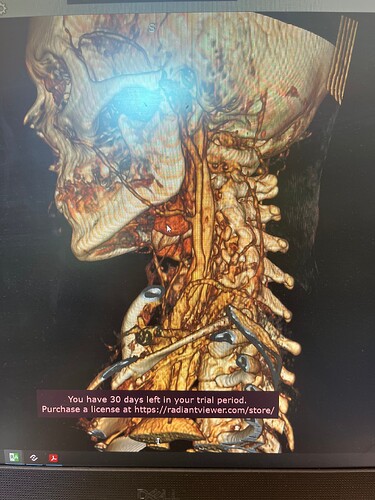

In your first & last pictures, you can see how close to your spine the greater horns of your hyoid are. Your whole hyoid looks like it’s been pushed back further in your neck than it should be possibly producing Hyoid Bone Syndrome (HBS).

Might want to check out left styloid process and ligament also. Can see it on the 3D but not all of it due to blood vessels. Might be contributing to the hyoid injury/problem if ligament is calcified.

So frustrating that you were doing well! The hyoid bone processes do look quite long & very close to your vertebrae, as the others have said, so worth looking in to if you can…